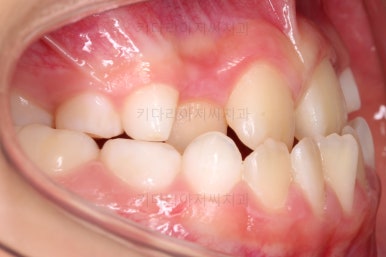

마찬가지로 초진 시 입안의 모습이에요.

아래 앞니가 윗니보다 앞에 있는 "반대교합" 즉, 거꾸로 물려있는 상황이었고요.

어금니 쪽을 보시면(왼쪽 위 사진) 윗니 어금니도 아래 어금니보다 안쪽으로 들어와 있는 "어금니 반대교합"도 있는 상황이었어요.

즉, 윗니가 있는 위턱뼈가 3차원적으로 작은 상황이었던거죠.

이렇게 아랫니들이 윗니보다 앞으로 나와있는 형태의 부정교합을 "앵글씨 3급" 부정교합이라고 합니다.